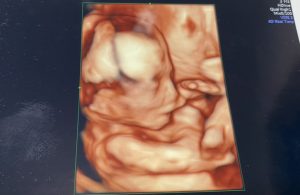

前回(妊娠4ヵ月:12w2d)のエコー写真

今回(妊娠5ヵ月:16w2d)のエコー写真

人間らしくなってました!

顔立ちもはっきりしてきて可愛い♡